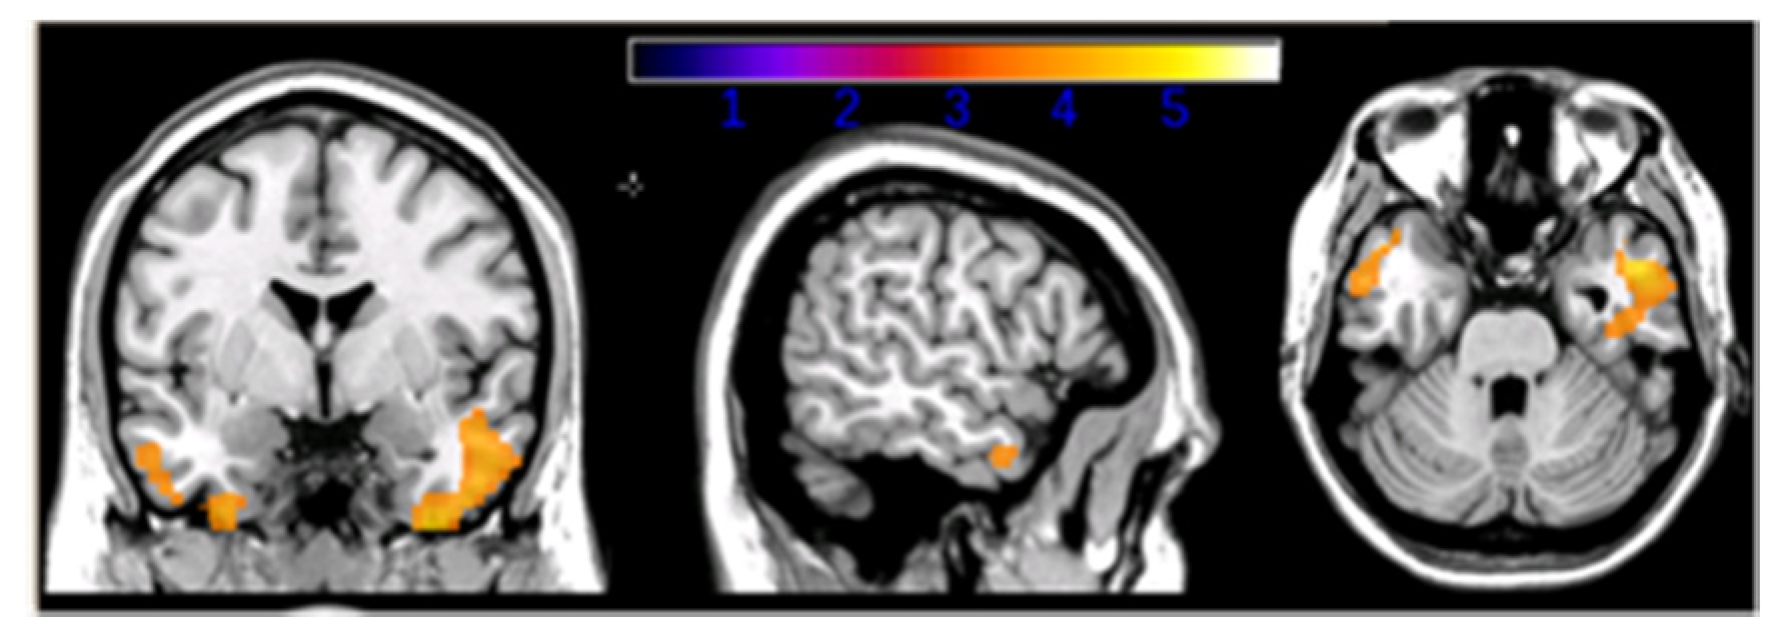

- Carapelle, E.; Serra, L.; Modoni, S.; Falcone, M.; Caltagirone, C.; Bozzali, M.; Avolio, C. How the cognitive reserve interacts with β-amyloid deposition in mitigating FDG metabolism: An observational study. Medicine 2017, 96, e5876. [Google Scholar] [CrossRef] [PubMed]

- Serra, L.; Cercignani, M.; Petrosini, L.; Basile, B.; Perri, R.; Fadda, L.; Spano, B.; Marra, C.; Giubilei, F.; Carlesimo, G.A.; et al. Neuroanatomical correlates of cognitive reserve in Alzheimer disease. Rejuvenation Res. 2011, 14, 143–151. [Google Scholar] [CrossRef]